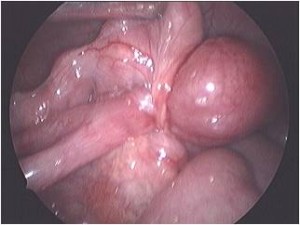

Acute scrotum is sudden onset of redness and swelling over the scrotum. This is associated with severe pain over the scrotum and sometimes lower abdomen and may be accompanied with nausea and vomiting.

Of the many causes of acute scrotum, the most common and important is Torsion of Testis. The testis is supplied by a single blood vessel and any torsion on this vessel may impede the blood supply to the testis. If urgent medical attention and intervention is not done, this may result in testicular gangrene and orchidectomy ( removal of the dead testis) may be needed.

The commonly misleading history given by the parents is that the child may have had a trivial trauma or an insect bite. However, for the clinician the golden rule should be ‘Any acute scrotum is testicular torsion unless proved otherwise’. Investigations like ultrasound and color doppler may be done to help in the diagnosis. However, in the event of any doubt, it is safest to do a surgical exploration of the scrotum. The other uncommon causes of acute scrotum are acute epidydymo orchitis, scrotal abscess, idiopathic scrotal oedema and torsion of appendix of the testis. ●

Acute Scrotum

Torsion Testis (Pre and Per operative photo)